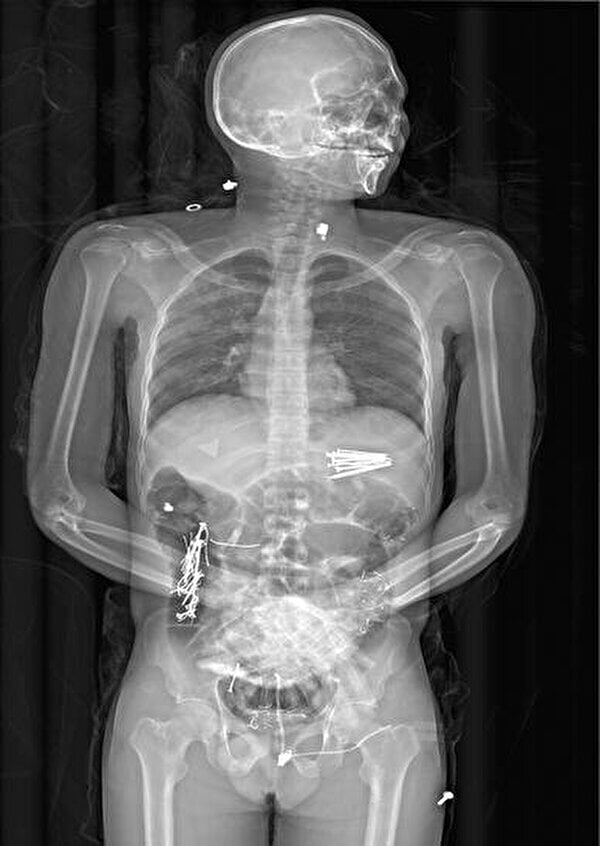

【閲覧注意】”異食症” で死亡した人間の体内、めちゃくちゃヤバい事になってた…(画像あり)

gif_animation アフリカの医師が公開した、「通常の人間が食べないものを日常的に食べてしまう摂食障害」の一つ、”異食症” で死亡した31歳男性の体内がめちゃくちゃヤバい事になってたギャラリー。カミソリや針金、クギなど…。[5]images